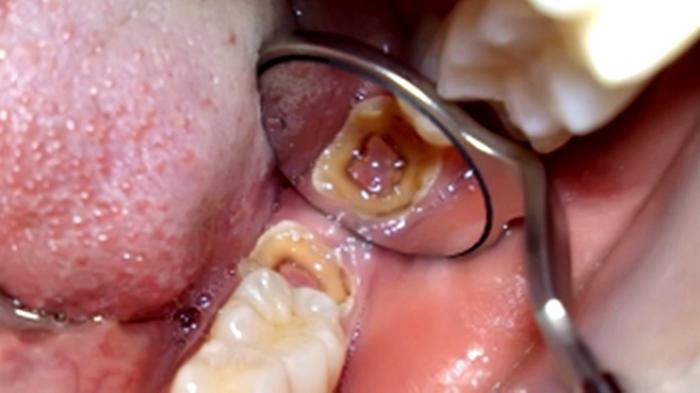

Walau sebenarnya, sakit gigi adalah masalah kesehatan yang umum terjadi dan seringkali muncul tanpa gejala pada awal mulanya. Rasa sakitnya yang bervariasi dari mulai tajam, berdenyut, sampai konstan.

Dari rasa sakit yang ditimbulkannya, sudah pasti bakal mengganngu aktivitas sehari-harinya Anda. Diluar itu, bila dibiarkan tanpa penanganan yang tepat, kerusakan gigi bakal bertambah parah hingga harus dicabut.

Yakni dapat disebabkan karena gigi yang berlubang, makan atau minum makanan atau minuman yang terlampau manis, terlampau asam atau terlampau dingin.